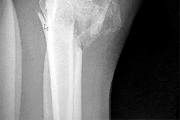

A 45-year-old male sustains the injury pattern depicted in the provided image. During surgical reconstruction of the lateral collateral ligament complex, identifying the correct isometric origin of the lateral ulnar collateral ligament (LUCL) on the distal humerus is critical. Where is this point located?

Correct Answer: At the center of the axis of rotation of the capitellum

Explanation:

The isometric point for the LUCL origin on the humerus is the center of the axis of rotation of the capitellum. Placing a graft or suture anchor at this specific geometric location ensures that the reconstructed ligament maintains relatively constant tension throughout the elbow's entire arc of flexion and extension.